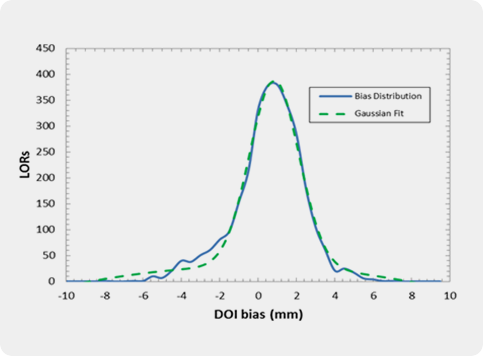

Several crystal-APD units and the corresponding frontend electronics are assembled in detector modules. Our APD-based detector module has 384 LYSO 2x2x20 mm crystals and covers a detection area of ~4x8 cm. One of the advantages the APDs is the capability of performing the double readout of the scintillation crystals, which allows to calculate the DoI of the detected photons. Associated to the fine detector pitch (2x2 mm) and the one-to-one coupling between crystal and APD pixels, the DoI capability permits an excellent spatial resolution of the order of 1.3 mm over the whole Filed-of-View.

The main spectroscopic characteristics of the Clear-PEM system are energy resolution for 511 keV photons of of 13.4%, coincidence time resolution of 2.8 ns (FWHM) and DoI resolution of 2.8 mm (FWHM).

Clear-PEM double readout scheme allows calculation of photon Depth of Interaction (DOI) and compensates blurring due to the parallax effect in PET resulting in an isotropic image resolution of 1.3 mm FWHM.